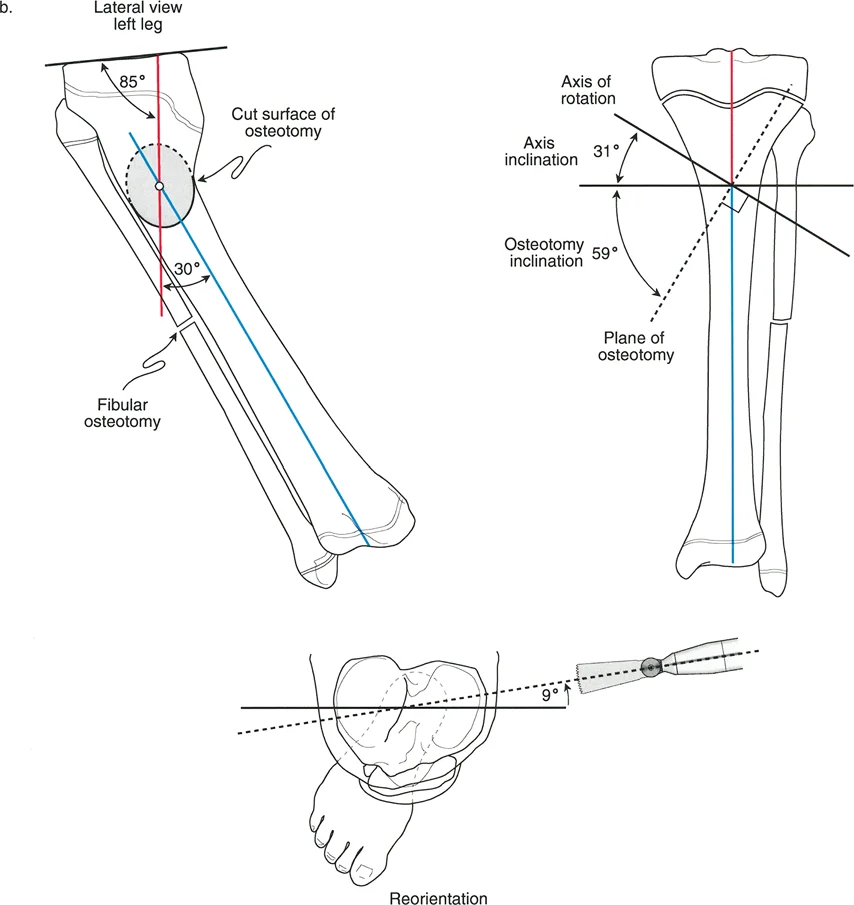

زوايا المفاصل في المستوى السهمي: الأبعاد الخفية للحركة

بينما تحدد المحاذاة في المستوى الأمامي (من الأمام) مشاكل التقوس والفحج، فإن المحاذاة في المستوى السهمي (من الجانب) تحدد التشوهات المتعلقة بالانثناء أو الامتداد المفرط، مثل الركبة المنحنية للخلف (Recurvatum) أو المنحنية للأمام (Procurvatum). توجيه المفاصل في هذا المستوى حيوي لاستعادة الحركة الطبيعية، خاصة ميلان الجزء الخلفي من عظم الساق، والذي يؤثر بشكل مباشر على شد الأربطة الصليبية في الركبة.

توجيه مفصل الركبة (المستوى السهمي)

الزاوية الظنبوبية القريبة الخلفية (PPTA)

تقيس PPTA ميلان الجزء الخلفي من سطح عظم الساق العلوي (اللقمة الظنبوبية). وهي الزاوية الخلفية المتكونة بين المحور التشريحي لعظم الساق وخط مفصل الساق القريب في الصورة الشعاعية الجانبية.

* القيمة الطبيعية المقبولة لـ PPTA هي 80 درجة ± 3.5 درجة (أو ما يعادل ميلاناً خلفياً بحوالي 10 درجات عن الخط العمودي).

هذا الميلان الخلفي ضروري لوظيفة الركبة الطبيعية، حيث يؤثر على كيفية عمل الأربطة الصليبية (الأمامية والخلفية) واستقرار الركبة. أي تغيير في هذه الزاوية يمكن أن يزيد من خطر إصابات الأربطة أو يسبب عدم استقرار في الركبة.